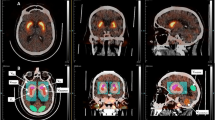

On the PD/Control cohort, per design, no differences were found in age or sex. As expected, PD patients had significantly higher bradykinesia, rigidity and RT (Table 2). Of the 86 participants in the DaT-SPECT cohort, 34 had an abnormal scan (positive DaT-SPECT group) while 52 patients did not (negative DaT-SPECT group) (Fig. 3A). Positive and negative group patients did not differ regarding age, sex or time since onset of symptoms (Table 3). Positive group patients presented higher bradykinesia and rigidity scores, but the two groups were not different regarding total tremor and RT MDS-UPDRS scores (Table 3). Next, we analysed the data collected from the motion sensor positioned in the lower back (Fig. 3B). The raw acceleration was filtered, a principal component analysis was performed, and the first component was used as the main axis of movement (Full details in the methods section). Given the oscillatory nature of tremor and in line with previous work37,38, we used spectral analysis of the accelerometer data to compare the different groups (Fig. 3B, bottom).

A Champalimaud Clinical Centre DaT-SPECT images were classified into positive (evidence of dopamine denervation) or negative (no evidence of dopamine denervation) based on standard clinical criteria. B Inertial sensor placement and orientation in patients’ lower back. Example of triaxial acceleration, along with the schematic representation of the signal pre-processing pipeline and extraction of the maximum spectral power between 4 and 6 Hz, with an example of the Welch power spectral density (bottom). C Left, Welch power spectrum (normalized to the mean power between 1 and 3 Hz) for the PD (blue) and Control (green) groups. Right, Comparison of the log of the maximum power spectrum. D Left, Welch power spectrum (normalized to the mean power between 1 and 3 Hz) for the Positive (red) and Negative (grey) groups. Right, Comparison of the log of maximum power spectral density in the 4–6 Hz band between the Positive and Negative groups. E log of maximum power spectral density (4–6 Hz) vs. Rest (left) and Action (right) tremor scores for PD, the Positive and Negative groups.